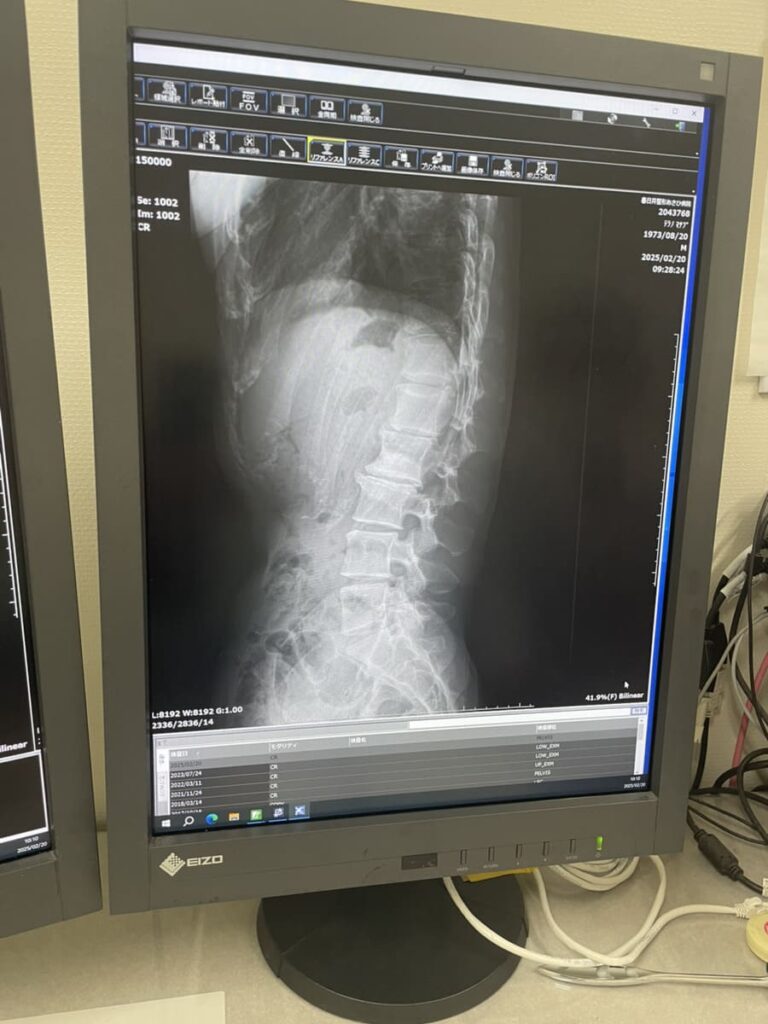

レントゲン写真では、変形のある腰椎以外にも椎間が狭くなっている所がありますし、S字カーブが崩れているように見受けられます。

側湾に関しては神経学としての

以前、作業療法士の方に教えてもらったのですが側湾は呼吸の確保を優先していくと良いとの話でした。(側湾の状態によって異なるとは思いますが)

側湾によって肺の動きに制限がかかって呼吸が浅くなっていないか?

動きの悪いと感じる肺の側を広げて(側屈)深い呼吸をしてまずは肋骨を前後左右に広げられる様に練習することも大切だと思います。